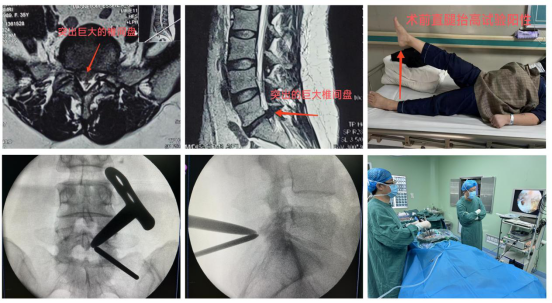

周至县人民医院骨科近期收治了一位35岁女性患者,主诉“右下肢抽痛、麻木半年,加重2月”,行走约50米后,右下肢疼痛难忍,严重影响生活质量。靳占奎副主任医师对患者进行了一系列检查和严格的鉴别诊断,认定该患者“腰椎间盘突出症”诊断明确,且患者经过半年以上的保守治疗无显著疗效,具有明确手术指征。靳占奎副主任医师指导县医院充分完善UBE技术必备的硬件条件,为患者顺利实施了“微创单侧双通道脊柱内镜下腰椎间盘髓核摘除术”。术后患者右下肢疼痛缓解,患者非常满意。

微创单侧双通道脊柱内镜(UBE)技术是治疗腰椎间盘突出症的经典微创手术方式,相较于其它微创手术,该技术入路更接近开放手术,学习曲线相对平缓,镜下视野更全面,操作通道可以应用类似开放手术的器械,安全性高。该手术目前是三级片

骨科脊柱微创手术治疗的一大特色。